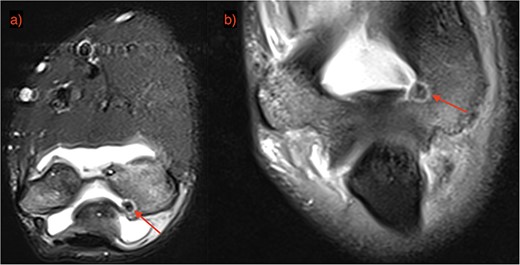

A 21-year-old man, who is right-hand-dominant, presented in our clinic with a localized and persistent pain in his right elbow joint that had been present for more than 6 months. Previously, the patient was treated by Rheumatologist for several months with initial diagnosis as idiopathic synovitis involving the right elbow and he was referred to us for a second opinion. He reported that the complains started when he was lifting weights in the gym. On physical examination, a swelling was noted and a restricted extension/flexion (−45°/115°) was present, while pronation/supination was within normal values. There was pain in terminal extension but also during the night. The neurovascular examination was normal. Laboratory tests and plain radiography results were normal. Subsequent MRI with contrast was performed after normal plain radiography results, and it revealed a focal nidus in olecranon fossa (Figs 1 and 2) consistent with an intra-articular OO. Then, a 3D CT scan was also performed for better localization of the tumor [3].

OO localization with contrast MRI: (a) coronal view and (b) frontal view.